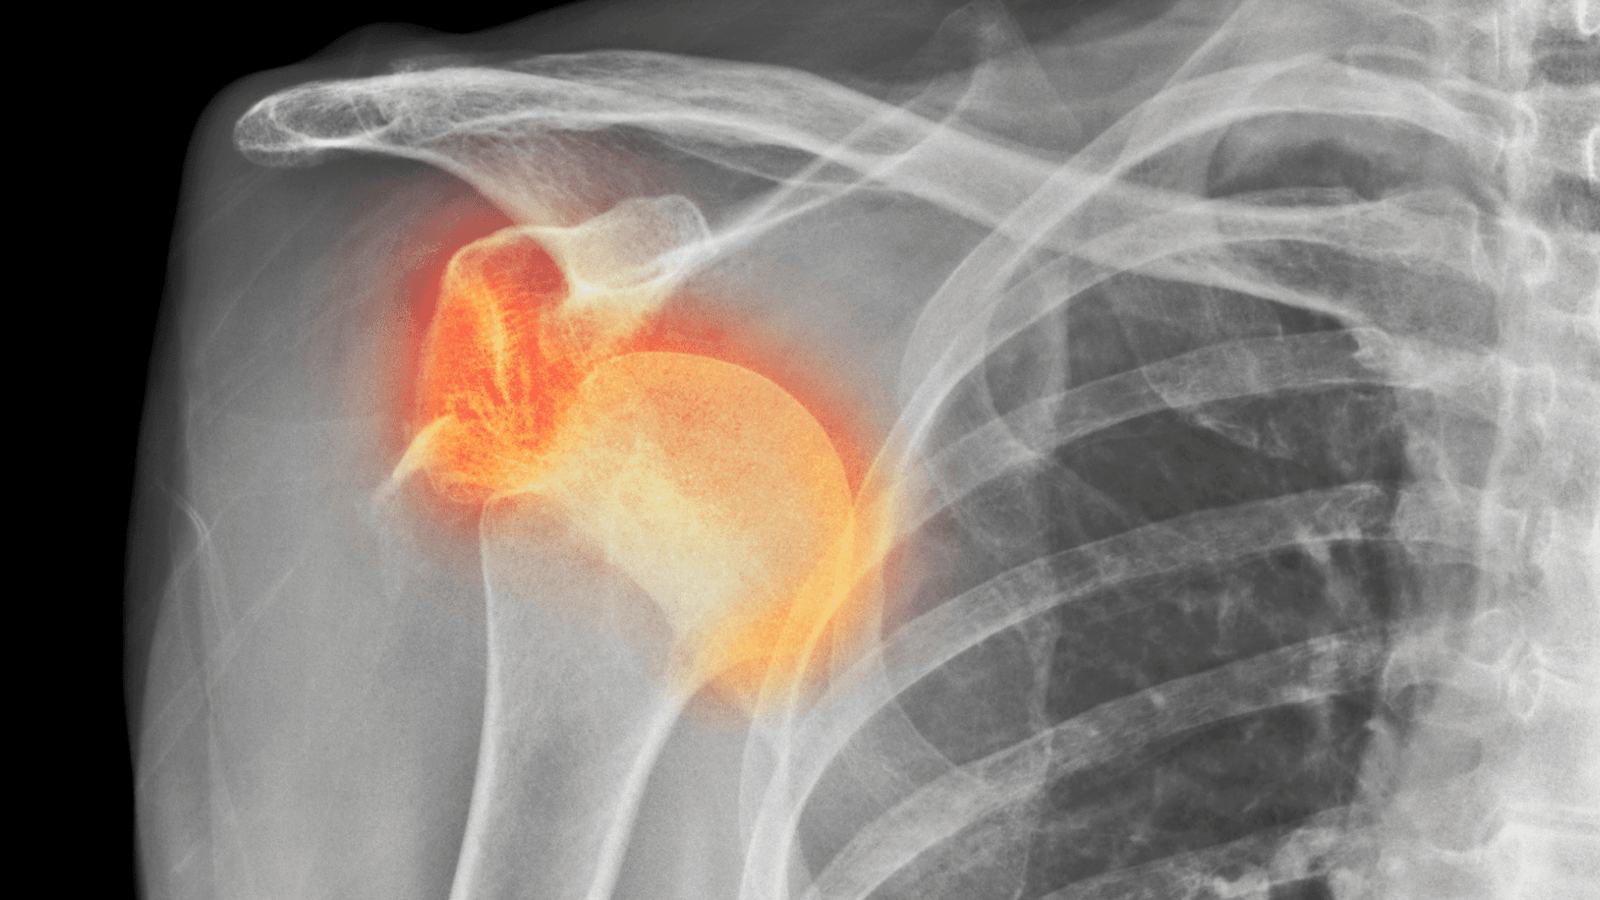

Recurrent Shoulder Dislocation

The shoulder is the most mobile joint in the body, which also makes it the most vulnerable to dislocation.

When a shoulder gets dislocated repeatedly, the condition is known as recurrent shoulder dislocation.

In most cases, the first dislocation causes a tear in the shoulder labrum — a ring-like structure that helps keep the shoulder ball inside the socket. If this tear does not heal properly, the shoulder becomes unstable and may slip out again, even with very minimal force.

The specific injury to the labrum that leads to repeated dislocations is called a Bankart’s lesion. To stop further dislocations, this lesion needs to be repaired surgically, a procedure known as Bankart’s repair.